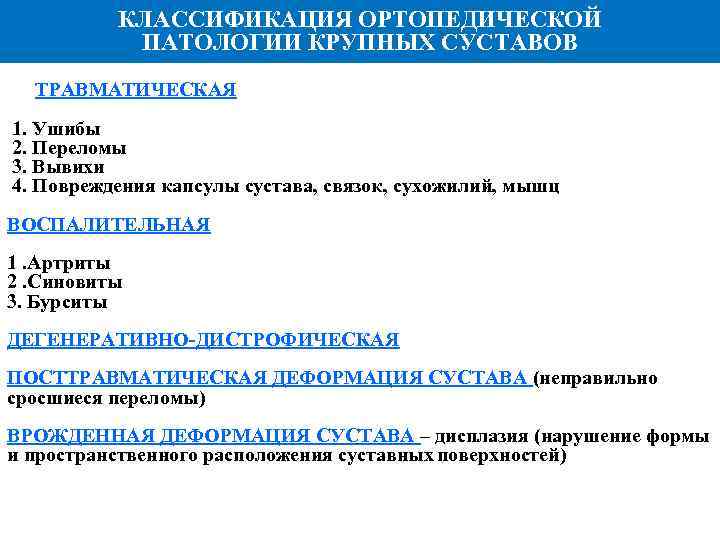

КЛАССИФИКАЦИЯ ОРТОПЕДИЧЕСКОЙ ПАТОЛОГИИ КРУПНЫХ СУСТАВОВ ТРАВМАТИЧЕСКАЯ 1. Ушибы 2. Переломы 3. Вывихи 4. Повреждения капсулы сустава, связок, сухожилий, мышц ВОСПАЛИТЕЛЬНАЯ 1. Артриты 2. Синовиты 3. Бурситы ДЕГЕНЕРАТИВНО ДИСТРОФИЧЕСКАЯ ПОСТТРАВМАТИЧЕСКАЯ ДЕФОРМАЦИЯ СУСТАВА (неправильно сросшиеся переломы) ВРОЖДЕННАЯ ДЕФОРМАЦИЯ СУСТАВА – дисплазия (нарушение формы и пространственного расположения суставных поверхностей)

КЛАССИФИКАЦИЯ ОРТОПЕДИЧЕСКОЙ ПАТОЛОГИИ КРУПНЫХ СУСТАВОВ ТРАВМАТИЧЕСКАЯ 1. Ушибы 2. Переломы 3. Вывихи 4. Повреждения капсулы сустава, связок, сухожилий, мышц ВОСПАЛИТЕЛЬНАЯ 1. Артриты 2. Синовиты 3. Бурситы ДЕГЕНЕРАТИВНО ДИСТРОФИЧЕСКАЯ ПОСТТРАВМАТИЧЕСКАЯ ДЕФОРМАЦИЯ СУСТАВА (неправильно сросшиеся переломы) ВРОЖДЕННАЯ ДЕФОРМАЦИЯ СУСТАВА – дисплазия (нарушение формы и пространственного расположения суставных поверхностей)